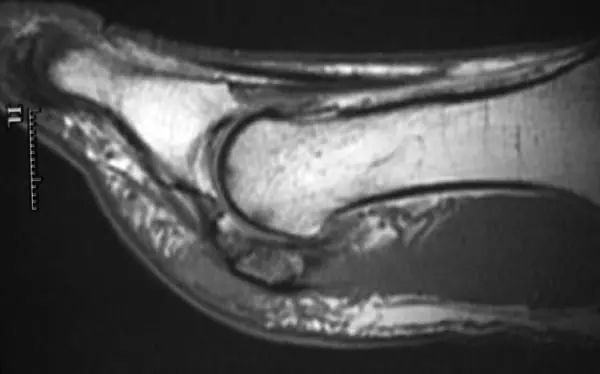

MRI of AVN of the sesamoid. The bone should be white like the other bones. The sesamoid is darker indicating lack of blood flow to the bone.

The sesamoid should be a white color similar to the other bones (green arrow). The sesamoid that is darker is damager and can lead to AVN (red arrows).

The bones should all be similar appearance of white. The tibial sesamoid is darker indicating damage to the bone.